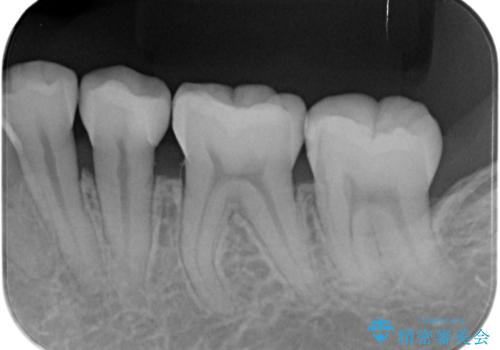

コンタクトカリエス

- レントゲンで虫歯(コンタクトカリエス)が見られたので拡大鏡で虫歯を取り除いた後、e-maxインレー(セラミックインレー)で治療を行いました。